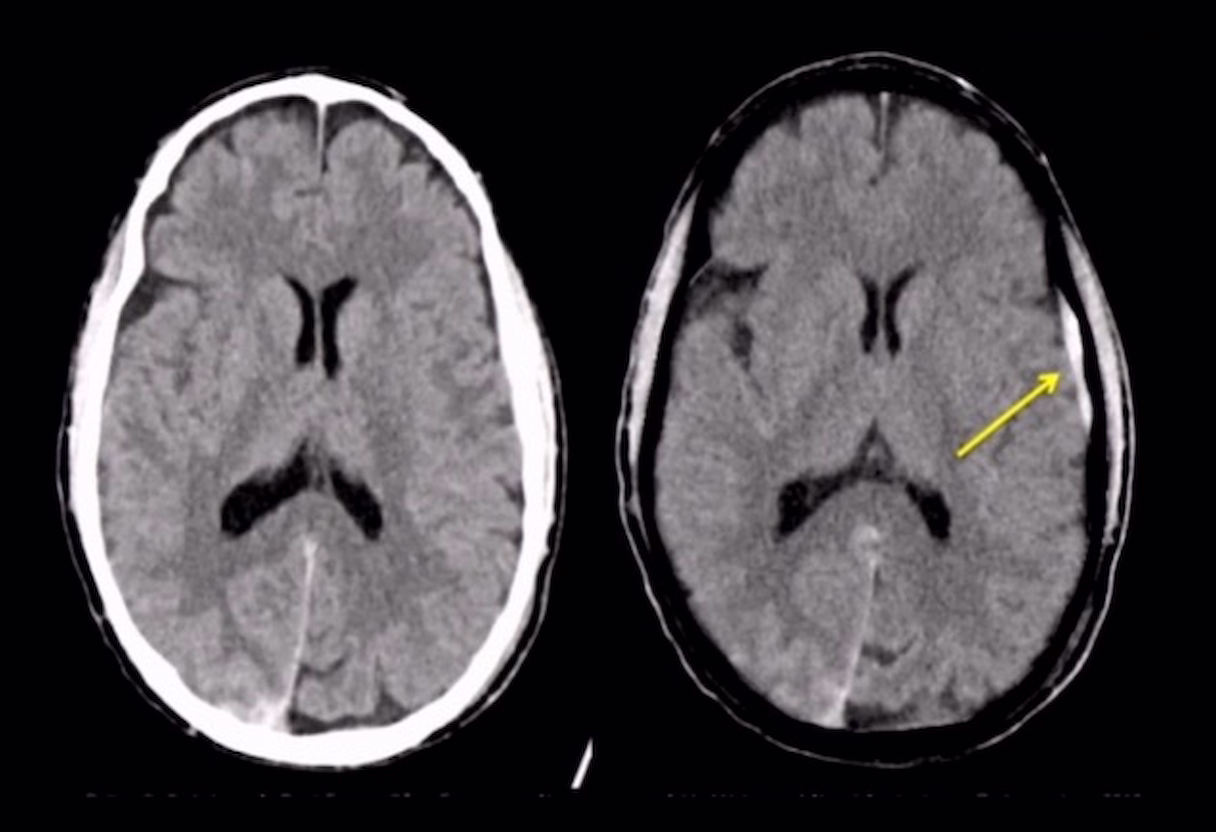

Comprehensive education for new and experienced staff, including advanced CT, protocol optimization, cardiac enhancement and dual-energy techniques.

Troubleshoot scans, adjust settings, and optimize protocols with live remote support for Siemens and GE systems. Perfect for new or experienced technologists seeking workflow improvements.

Standardize imaging, reduce repeats, and ensure compliance with custom protocol reviews and workflow audits. Achieve consistent, high-quality results across every site.